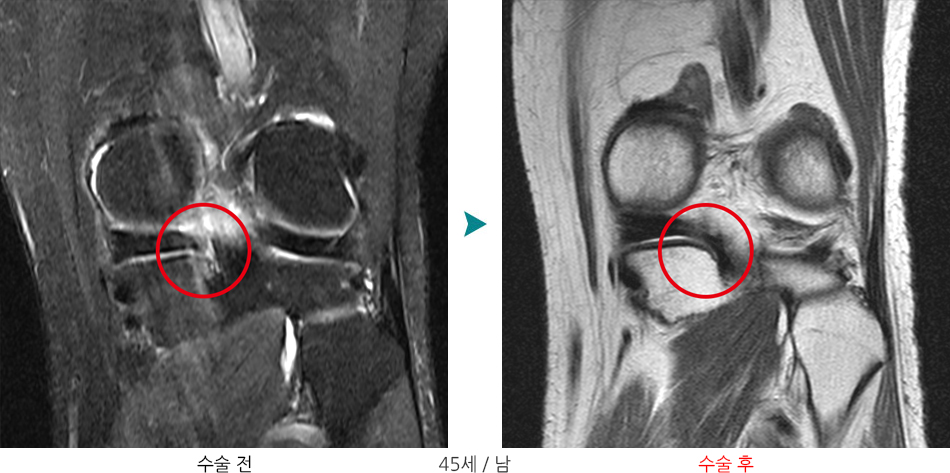

이 반월상 연골이 외상이나 퇴행성으로 인해 손상되거나 파열이 되어 통증이 나타나는 질환을 말합니다.

증상 및 파열 양상에 따라 관절경을 이용한 내시경 수술을 받게 되며 봉합술 내지는 절제술을 시행하게 됩니다.